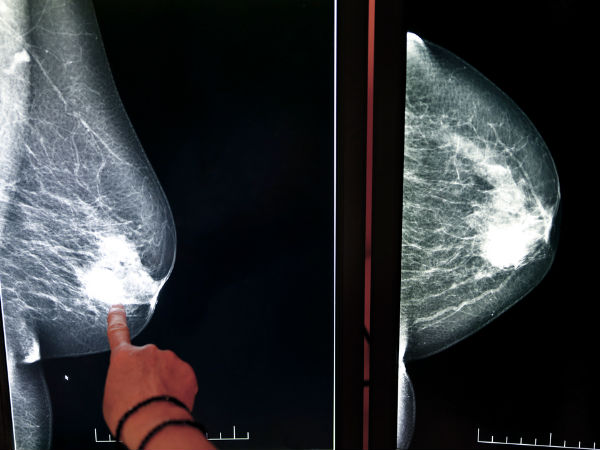

ಸ್ತನಗಳ ಒಳಭಾಗದ ಅಂಗಾಂಶಗಳಲ್ಲಿ ಯಾವುದಾದರೊಂದು ಅಂಗಾಂಶ ಹೆಚ್ಚು ಬೆಳೆದು ಸಾಂದ್ರೀಕೃತಗೊಂಡರೆ ಇದು ಗಡ್ಡೆಯ ರೂಪ ತಳೆಯುತ್ತದೆ. ಇದೂ ಸ್ತನಗಳ ವ್ಯತ್ಯಾಸಕ್ಕೆ ಪ್ರಮುಖ ಕಾರಣವಾಗಿದೆ. ಕೆಲವು ಗಡ್ಡೆಗಳು ನಿರಪಾಯಕಾರಿಯಾಗಿದ್ದರೆ ಕೆಲವು ಕ್ಯಾನ್ಸರ್ ರೂಪವನ್ನೂ ತಳೆಯಬಹುದು. ಕೆಲವು ಸಂದರ್ಭಗಳಲ್ಲಿ ಸ್ತನಕ್ಕೆ ಬಿದ್ದ ಪೆಟ್ಟಿನಿಂದಾಗಿಯೂ ಗಡ್ಡೆ ಮೂಡಬಹುದು. ಇಂದು ಲಭ್ಯವಿರುವ ಮ್ಯಾಮ್ಮೋಗ್ರಾಫಿ ಉಪಕರಣಗಳಿಂದ ಈ ಗಡ್ಡೆಗಳನ್ನು ಪರೀಕ್ಷಿಸಿ ಸೂಕ್ತ ಪಡೆಯುವುದು ಅಗತ್ಯ ಇನ್ನೊಂದು ಕಾರಣವೆಂದರೆ ಸ್ತನಗಳ ಒಳಗಣ ನರಗಳು ತಿರುಚಿ ಗಂಟುಗಳಾಗಿ ಹಗ್ಗವೊಂದನ್ನು ಮಡಚಿ ಒಳಗಿಟ್ಟಂತೆ ಕಾಣುವುದು (fibrocystic breasts). ಇದು ಅಪಾಯಕಾರಿಯಲ್ಲದಿದ್ದರೂ ವೈದ್ಯರಿಂದ ಪರಿಶೀಲಿಸಿ ಸಲಹೆ ಪಡೆಯುವುದು ಅಗತ್ಯ.